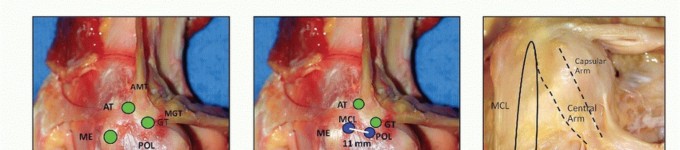

The posterior border of the superficial MCL and the anterior border of the POL are identified, and a vertical incision is made along this interval, exposing the deep MCL. - TECH FIG 1 • A. None of the tendons or ligaments attach directly on the osseous landmarks. B. POL femoral attachment is 1.4 mm distal and 2.9 mm anterior to the GT. Distance between the MCL and POL

attachment sites is 11 mm. C. POL anatomy: Superficial arm: thin fascial expansion that runs parallel and posterior to the MCL. Central arm: largest and thickest part. Firm attachment to the tibia and medial meniscus (MM). Capsular arm: thin fascial expansion, which blends with the posteromedial capsule.

AMT , adductor magnus tendon; AT, adductor tubercle; MGT, medial head of gastrocnemius; GT, gastrocnemius tubercle; ME, medial epicondyle; POL, posterior oblique ligament; MCL, medial collateral ligament; SM, semimembranosus. (Courtesy of Charles H. Brown, Jr., MD.)

A spinal needle is often useful to help localize the medial joint line. Anatomy of the medial side of the knee (TECH FIG 1A-C) -